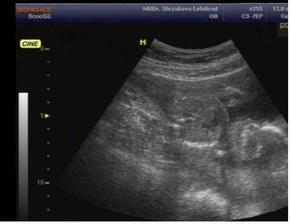

12.1.(10+1) další kontrola - mám obrázek z ultrazvuku - NÁDHERA .......

5.2. (13+5) utz bříška - kontrola nosní kůstky, orgánů, končetin - máme vše co tam být má a jsme vpořádku. UF... NT sreening dopadl výborně......

30.3. (21+3) velký ultrazvuk - tak naše stydlínování pokračuje (nebo je to maximálně poslušný dítě), jelikož ani paní doktorce neukázal, jestli bude kluk nebo holčička - my to vědět nechceme, proto poslušné dítě 🙂. Ale neukázal jí ani pusinku, tak na tu se podíváme příště. Jinak je vše v naprostém pořádku a mimís váží 375g........TP dle UTZ 12.8.

10.6. (31+3tt) velký ultrazvuk - byl i manžel. Váha 1494g, mimísek je něco menší, ale zatím se nemusím stresovat, ke konci těhu to ohlídáme, aby bylo vše vpořádku. Mimísek má hlavičku dole, což je taky dobrý, tak snad to bude pokračovat zdárně až do konce 🙂 TP dle Utz až 17.8. ...........